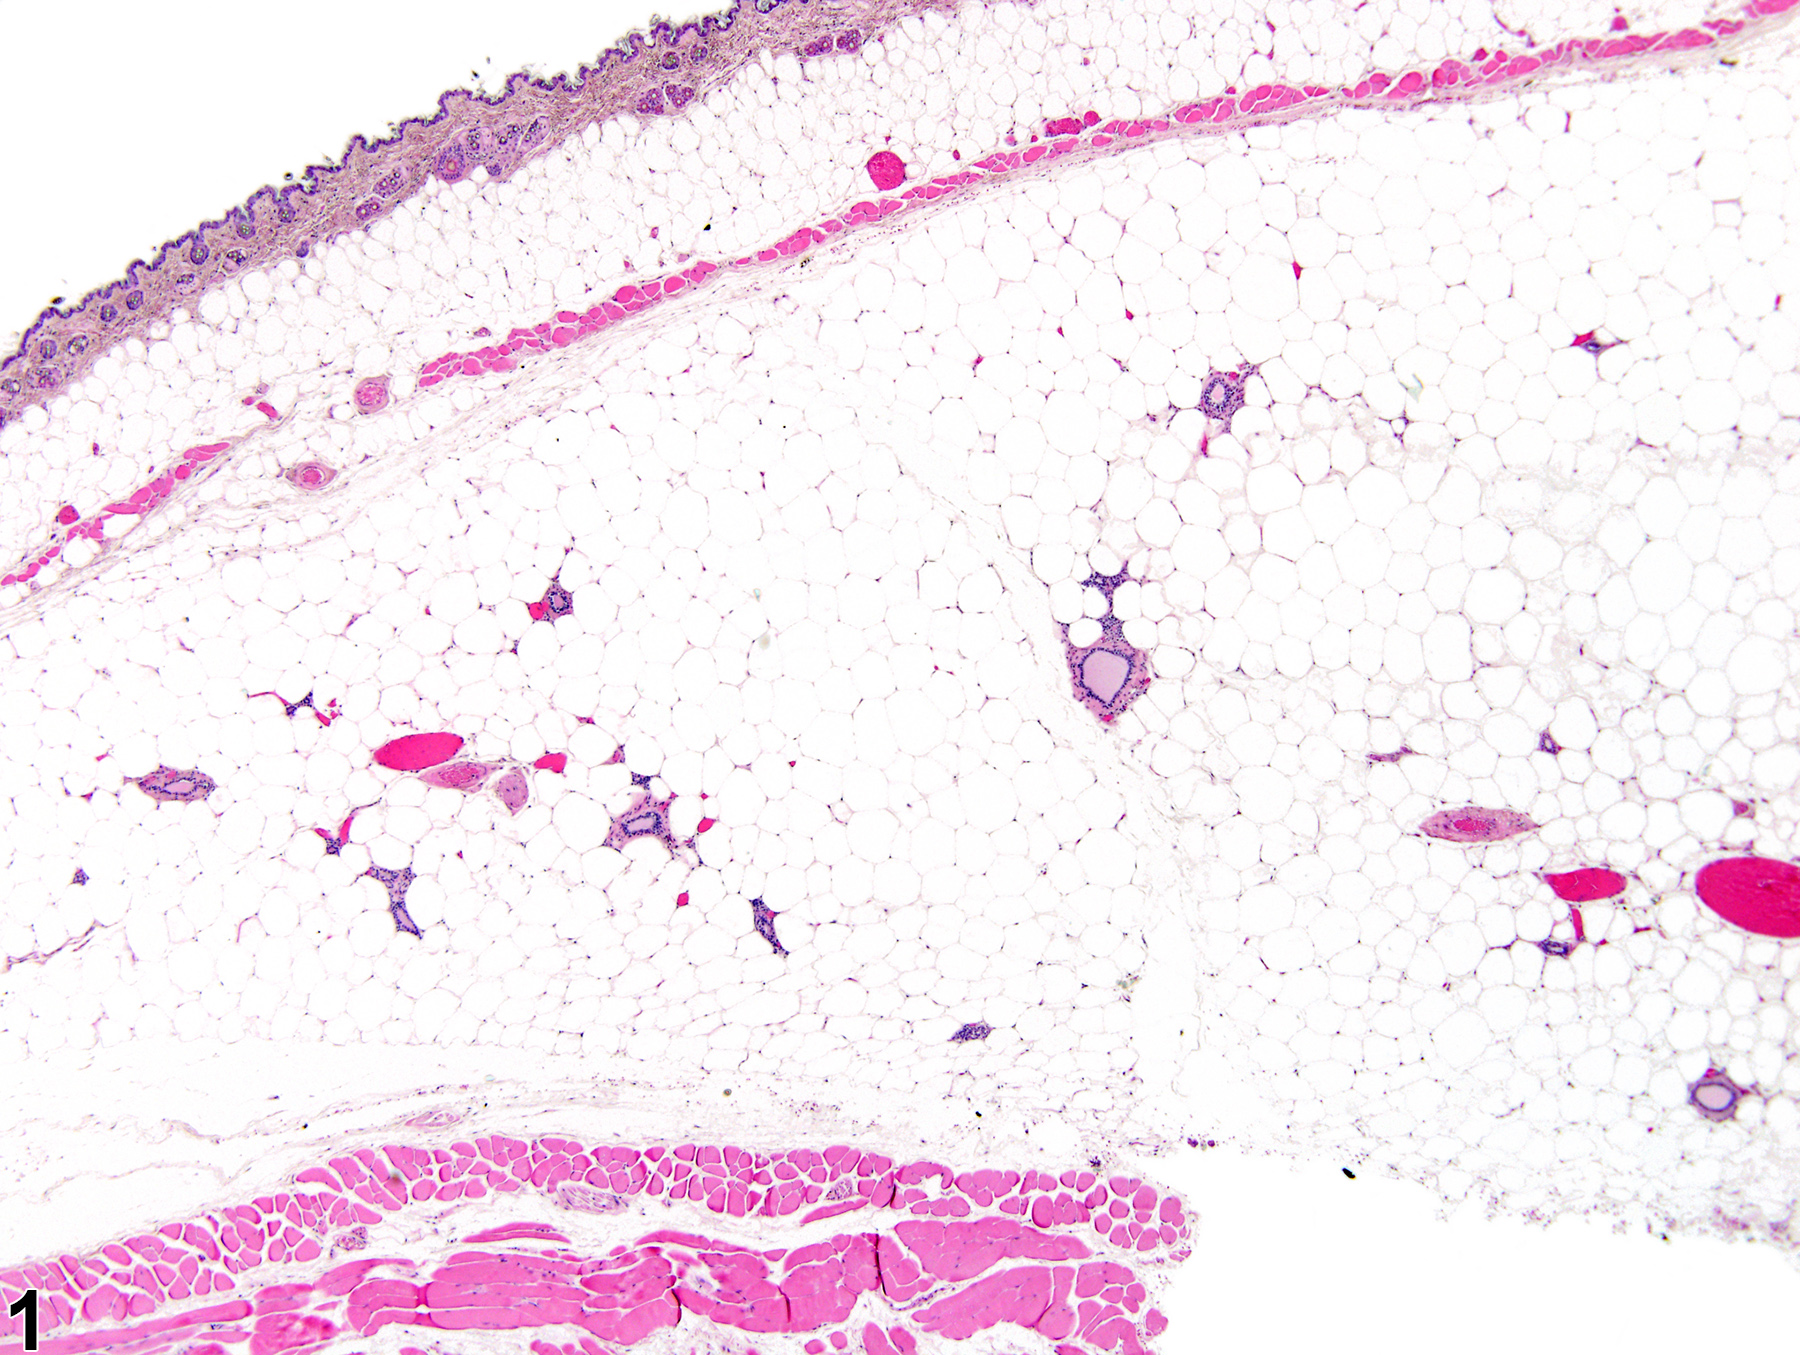

Diffuse atrophy of the normally abundant mammary gland adipose tissue (fat pad) often occurs in rats and mice suffering from weight loss or cachexia due to various causes, such as systemic disease, malignant neoplasia, or inability to feed due to malocclusion. As such, mammary gland fat atrophy is a common ancillary finding in animals that die or become moribund due to miscellaneous causes. Compared to a normal mammary gland (Figure 1), mammary gland fat pad atrophy (Figure 2) is characterized by generalized depletion and decreased size of the fat pad adipocytes, with concurrent condensation of the normal fibrous stroma, decreased numbers of tubule-alveolar profiles, and thinning of the lining epithelium. This results in less separation between alveoli and ducts, giving the impression of an overall more cellular gland, which should not be mistaken for hyperplasia or proliferation.

Mammary gland - Normal in a female B6C3F1/N mouse from a chronic study. Normal mammary gland with well-developed mammary fat (adipose) pad.